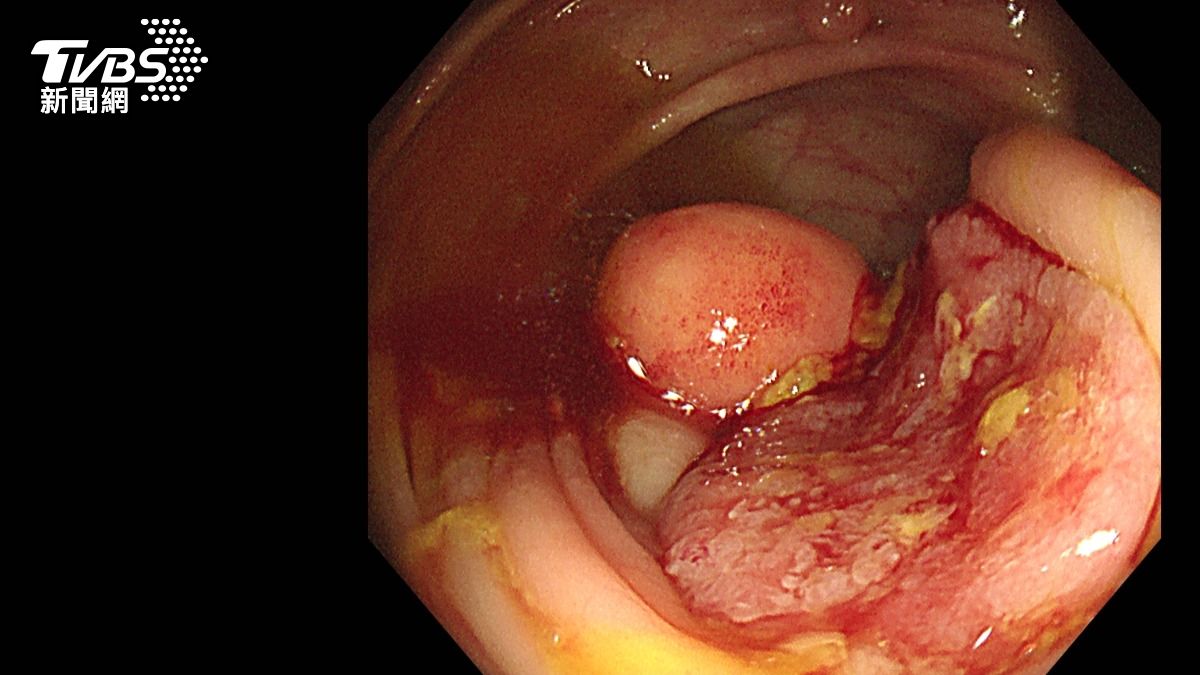

台中市一名64歲的蔡姓男子,平時生活單純,沒有抽菸、不良嗜好,但因為有肺癌家族史,近日仍照往例前往豐原醫院健檢,結果經胸腔外科醫師蕭凱宇檢查,蔡男雙側肺部有10多顆大小不一的肺部結節,評估確診肺腺癌,對此,蕭凱宇也提醒,肺癌早期沒有明顯症狀,,由於肺部缺乏痛覺神經,往往出現血痰、胸痛、胸悶、喘、骨痛、頭痛時,已經是中晚期,五年存活率也將大幅下降。